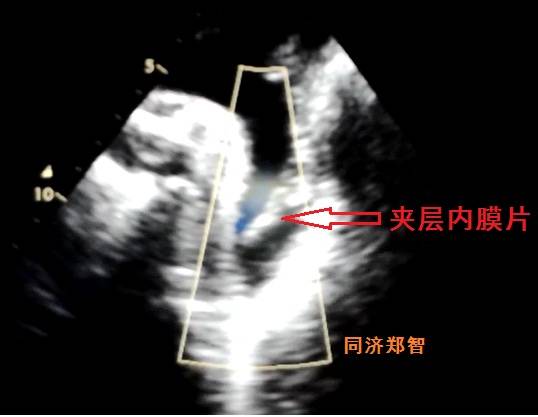

有时在彩超中也可以观察到内膜片,但其准确性不高,存在假阴性和假阳性的可能。

图16